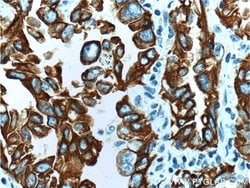

This antibody is specifically against KRT7.

Cytokeratin 7 blocks interferon-dependent interphase and stimulates DNA synthesis in cells. Involved in the translational regulation of the human papillomavirus type 16 E7 mRNA (HPV16 E7).Specifications

| Immunocytochemistry, Immunofluorescence, Immunohistochemistry (Paraffin), Immunoprecipitation, Western Blot | |